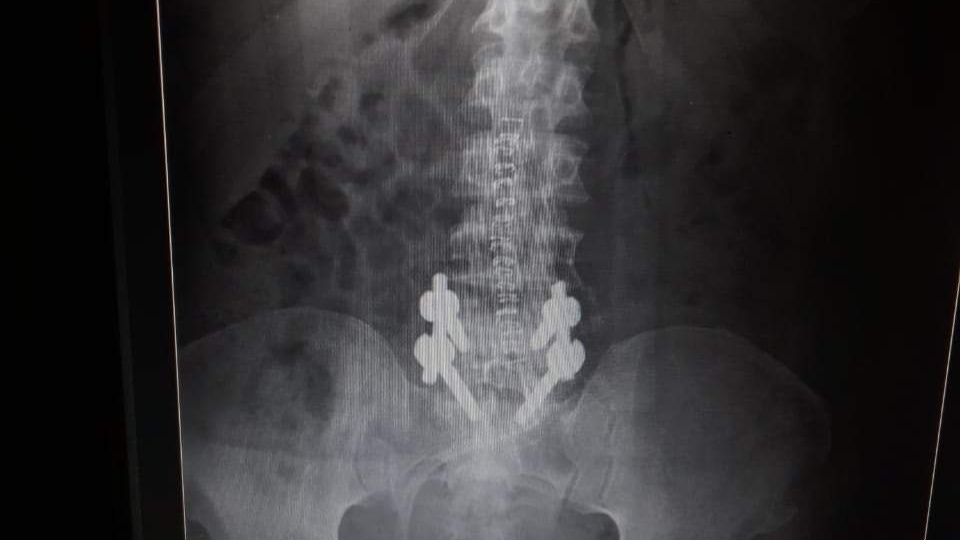

وأوضح مدير مستشفى ملوي التخصصي، أنه حضر إلى المستشفى مريض في العقد السابع من عمره يعاني من التهاب صديدي شديد بالفقرات القطنية ويعانى من أنيميا شديدة وفصيلة دم نادرة. O -ve.

حيث تم تحضير المريض وعمل فتح من البطن لتنظيف الالتهاب الصديدى ثم عمل جراحة أخرى من الظهر لتثبيت الفقرات.

وتابع الدكتور أحمد عمر مدير مستشفى ملوي التخصصي: أن المريض الآن فى حالة جيدة، وتم إجراء الجراحة له بوحدة العمود الفقري بمستشفى ملوى التخصصي بواسطة رئيس وحدة العمود الفقرى، للأستاذ الدكتور خالد عمران ثابت، أستاذ جراحة العظام والعمود الفقرى بمستشفى جامعة المنيا، وبمعاونة دكتور مصطفى جاويش أخصائي جراحة العظام والعمود الفقري بمستشفى الهلال ودكتور أحمد سيد، نائب جراحة العظام بمستشفى ملوى.